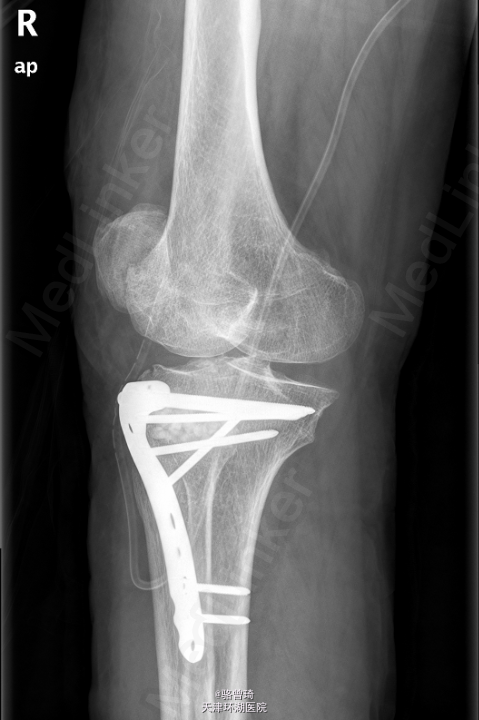

初步诊断:右胫骨平台粉碎性骨折.全麻下行行“右胫骨平台骨折切开复位内固定术+人工骨植骨术”。

术后予克林霉素0.9g静滴bid预防感染,补液,护胃,镇痛,保持水电解质酸碱平衡等对症支持处理。每月门诊复查X片,在专科医师指导下功能锻炼,禁下地负重行走。